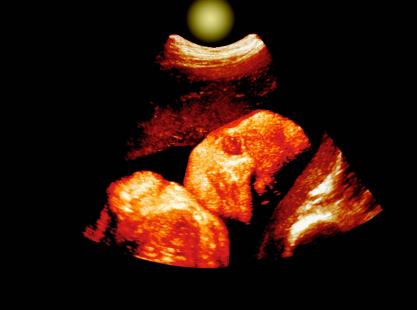

FOETUS ECHOGRAPHIE 3DVisage d'un foetus de 30 semaines, echographie 3DSimilaires, Similaire,...

Crédit photo : (c) BSIP 2000 #0231400